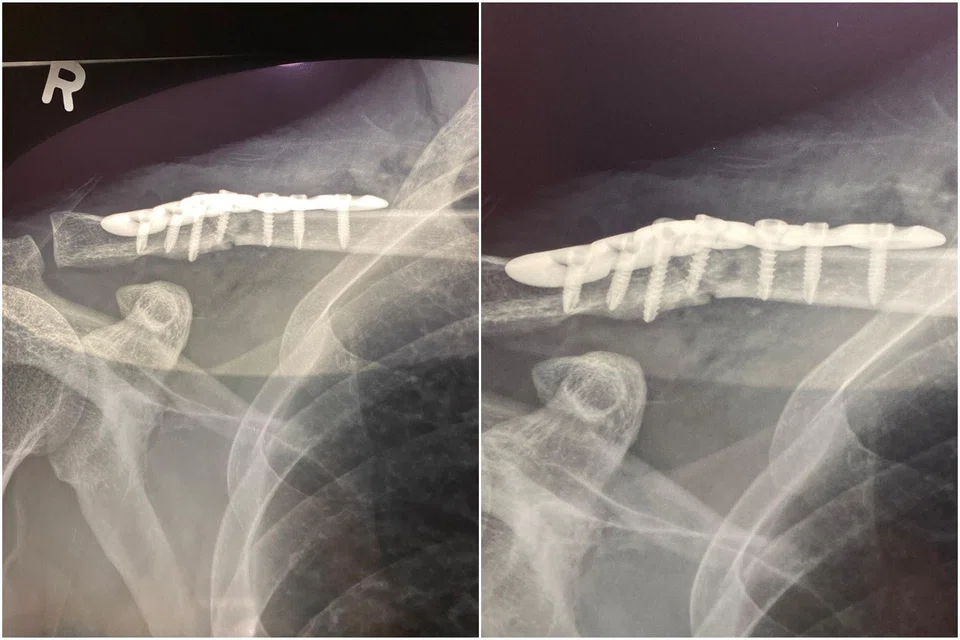

In January 2025, another cyclist sustained a collarbone fracture after the front tyre of his bicycle ran into a sharp metallic object along the same road, causing him to fall off.

Mr Lee, 43, who did not want to give his full name, had to wear an arm sling for three weeks and was on hospitalisation leave for 60 days.

He has not returned to cycling – something he used to do three or four times a week.